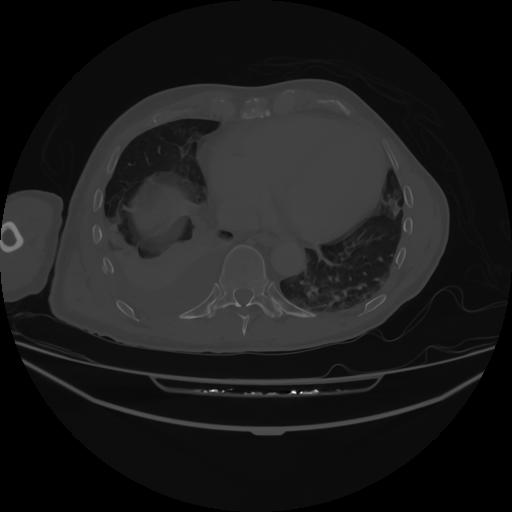

5 CUERPO,CE,Vol,1.0,CUERPO,,